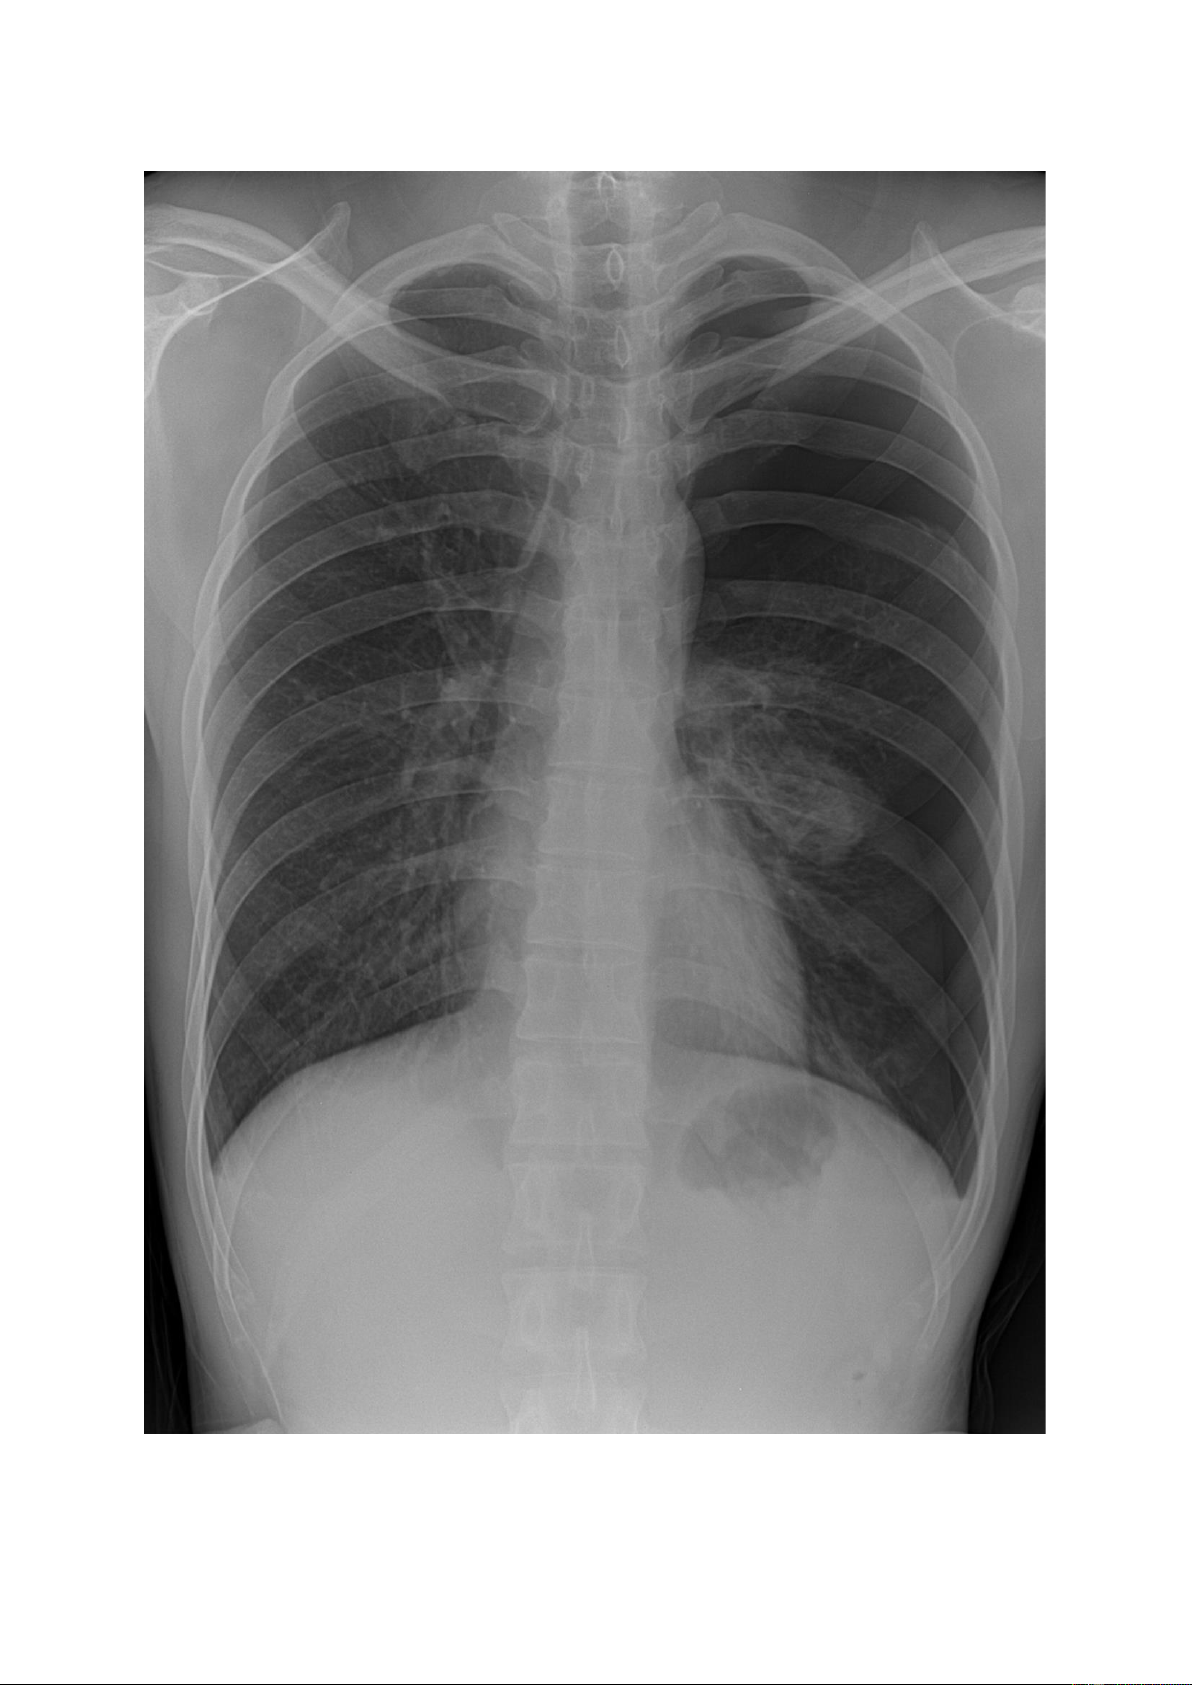

THỰC HÀNH ĐỌC PHIM X QUANG TIM PHỔI

I. TRIỆU CHỨNG TỔN THƯƠNG PHỔI TRÊN X QUANG 1.

Tổn thương mờ: (màu trắng trên phim X quang âm bản) có thể khu trú (đơn độc)

hoặc lan tỏa (số lượng nhiều).

Kích thước lấy chiều dài nhất tổn thương so với chiều cao 1 khoang gian sườn (~2,5 – 3cm). 1.1.

Nốt mờ nhỏ (hạt kê): là tổn thương có kích thước ≤ 3mm, do quan sát bằng

mắt thường nên nếu có số lượng nhiều sẽ thấy các tổn thương có kích thước đều nhau. lOMoAR cPSD| 22014077 1.2.

Nốt mờ lớn: là tổn thương có kích thước >3mm và < 3cm, số lượng có thể đơn

độc hoặc nhiều, kích thước có thể đều hoặc không đều, đậm độ cản quang khác nhau. lOMoAR cPSD| 22014077 lOMoAR cPSD| 22014077 1.3.

Khối mờ: là tổn thương có kích thước ≥ 3cm; số lượng có thể đơn độc có thể

nhiều. Nếu số lượng nhiều sẽ thấy các khối kích thước đều hoặc không đều nhau, đậm độ cản quang khác nhau. lOMoAR cPSD| 22014077 lOMoAR cPSD| 22014077 1.4.

Đám mờ: là tổn thương có sự tập trung của các nốt mờ theo vùng tạo thành

hình ảnh vùng mờ không đồng đều, không rõ bờ của vùng tổn thương đó. lOMoAR cPSD| 22014077 1.5.

Dải mờ - dải xơ: dải mờ là tổn thương mờ tạo thành một hoặc nhiều vệt (màu

trắng) dài ngắn khác nhau, dải xơ thường là di chứng để lại của dải mờ khi hồi phục

nên đậm độ cản quang cao hơn dải mờ. lOMoAR cPSD| 22014077 lOMoAR cPSD| 22014077 1.6.

Vôi hóa: là tổn thương có đậm độ cao (trắng đậm trên phim), tổn thương có

thể đơn độc hoặc lan tỏa (nhiều). lOMoAR cPSD| 22014077 lOMoAR cPSD| 22014077

2. Tổn thương quá sáng

Là hình ảnh tổn thương có màu đen hơn mô phổi lành xung quanh. Nếu tổn thương có nhìn

thấy mạch máu đi qua chứng tỏ thuộc vùng mô phổi, nếu tổn thương sát với bờ ngoại vi phổi

không thấy phân bố mạch máu bên trong thường gặp trong tràn khí khoang màng phổi. lOMoAR cPSD| 22014077